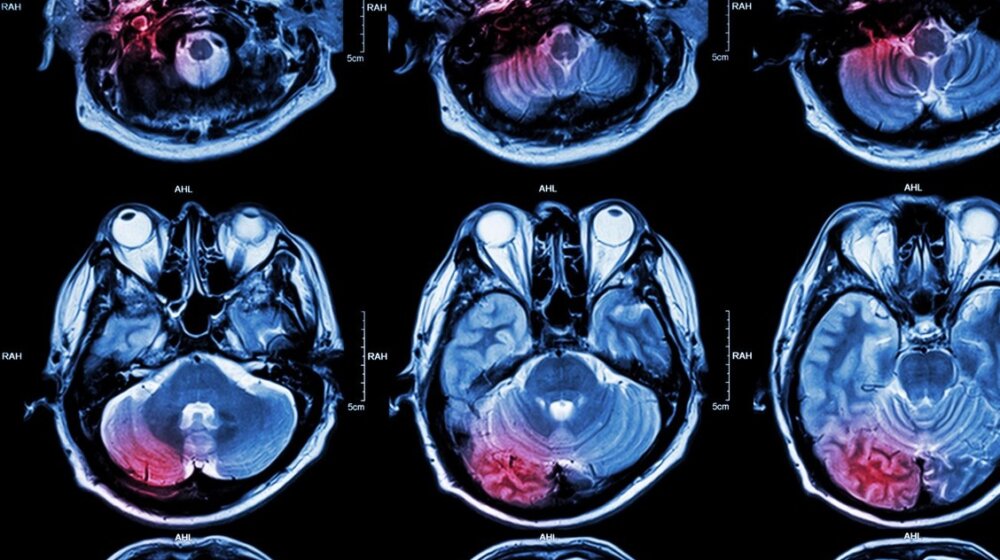

Tumor na mozgu, foto: Puwadol Jaturawutthichai / Alamy / Alamy / Profimedia

Tumor na mozgu, foto: Puwadol Jaturawutthichai / Alamy / Alamy / ProfimediaPostoji mnogo vrsta tumora mozga, a mogu biti maligni ili benigni. Kada su u pitanju maligni tumori, neki od njih nastaju u mozgu, pa se nazivaju primarnim tumorima mozga. U drugim slučajevima, maligni tumor se širi iz drugog dela tela u mozak, što dovodi do sekundarnih, metastatskih tumora mozga, kako piše Centar zdravlja, a prenosi N1.hr.